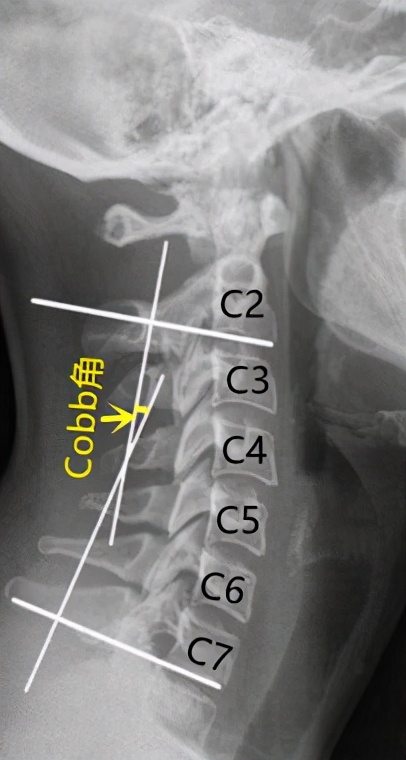

当我们颈肩疼痛不适到脊柱外科门诊拍X线片时,影像报告中有时会提到“颈椎变直”、“颈椎反曲”,往往会引起人们困惑。在颈椎X线侧位片上,颈2与颈7椎体下缘垂线的交角(Cobb角)正常约-10°左右。

颈椎侧位X线Cobb角的测量方法,正常曲度时Cobb角为负值,约-10°左右

当Cobb角接近0°时,反映我们的颈椎生理前凸基本消失,颈椎呈现一条变直,即发生了颈椎生理曲度变直;当Cobb角大于0°时,表明颈椎曲度发生了反转,由前凸变为后凸,即发生了颈椎反曲。